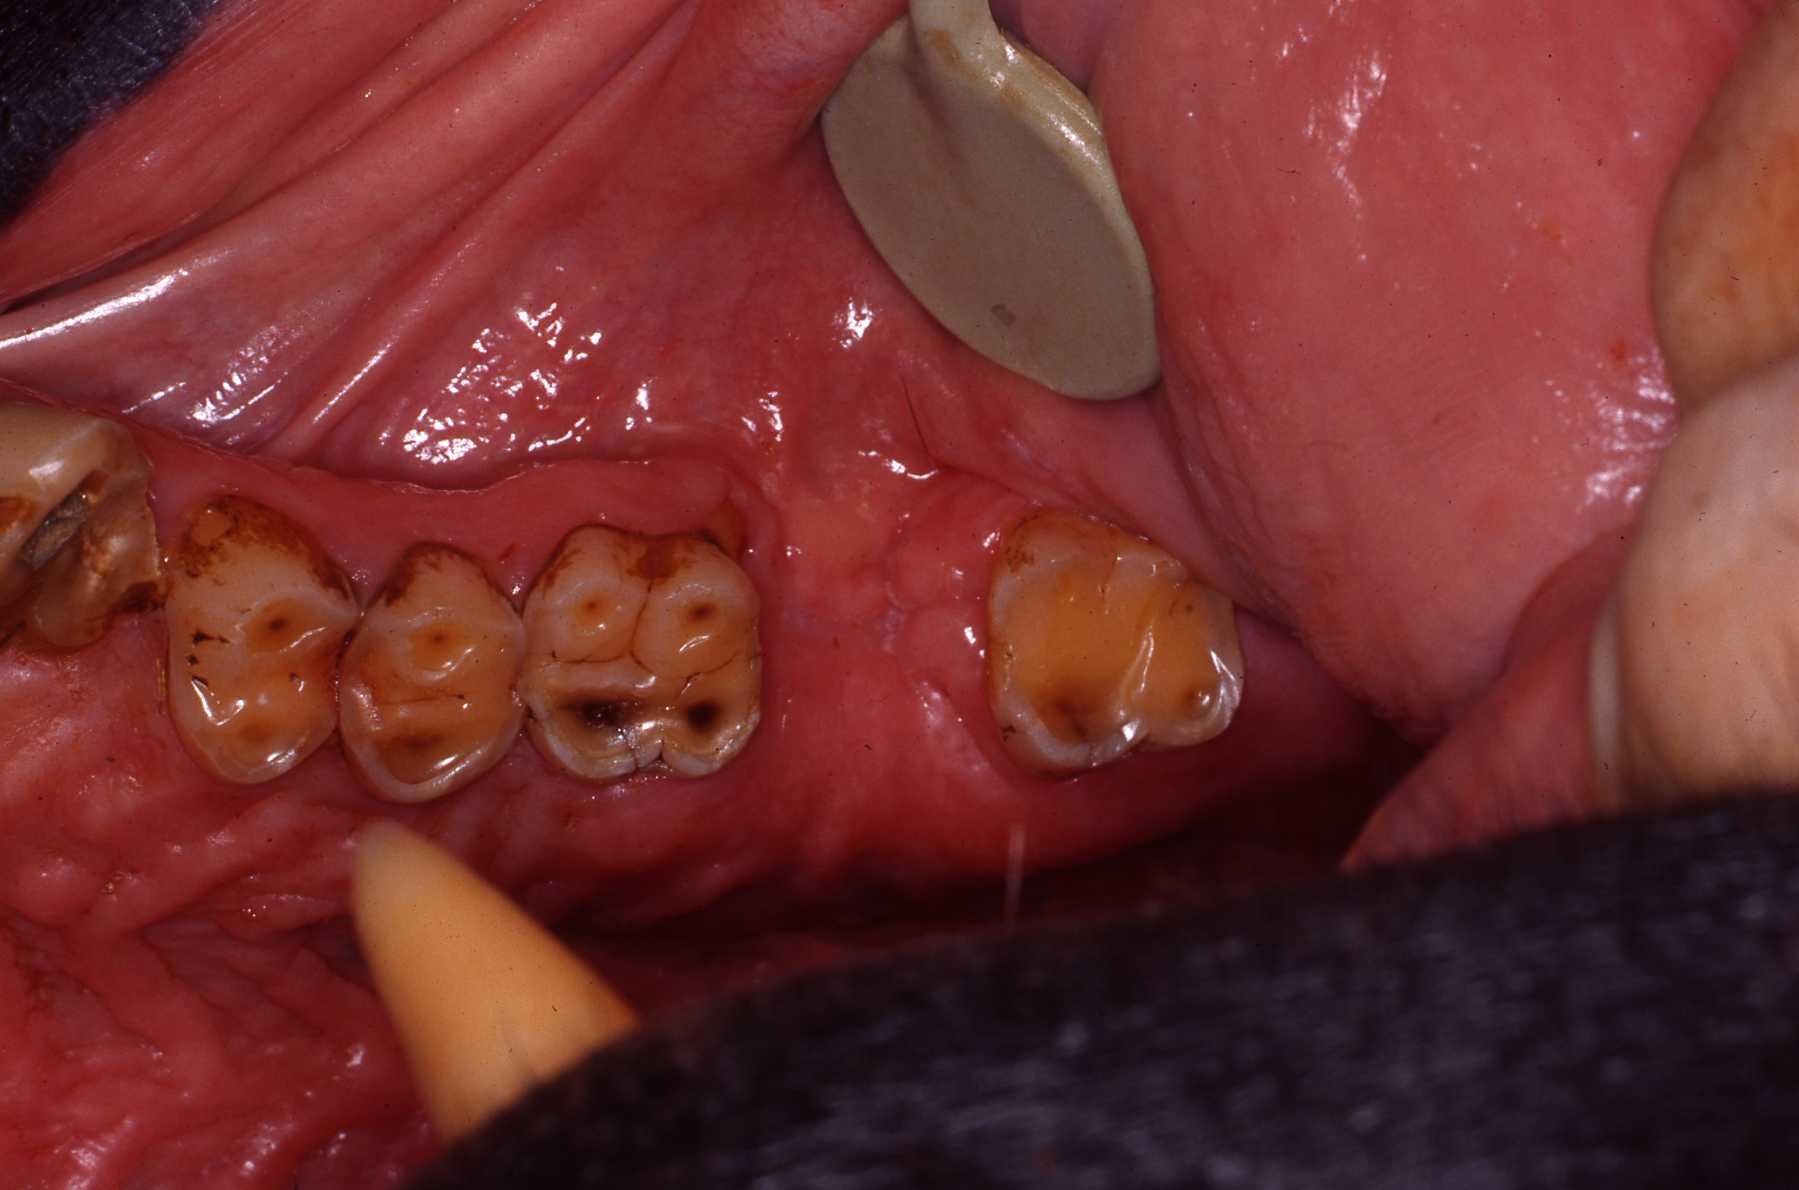

I frequently encountered caries in many animal groups when I began serving as a consultant. Until the early 1980s comprehensive veterinary care was not commonly provided in zoos, so physical and cursory oral and dental exams were only done when significant problems were already present. Proper diets had not been researched and keepers often provided their charges with sweet treats that led to tooth decay. Fortunately, zoo diets are scientifically developed now and keepers know to not provide improper treats.

I have also encountered significant dental attrition due to bruxism in many primate species. The psychological stress of confinement certainly contributes to such habits. Again, zoo keepers are very aware of such issues and these are addressed in many effective ways. Another habit related to stress, regurgitation of food and reingesting it, causes very significant damage to the entire periodontium, leading to loss of teeth. See Dr. John Huffs' on treating Tino at Salt Lake City zoo. I examined Tino when he was young at our zoo. He already had the regurgitation habit then.